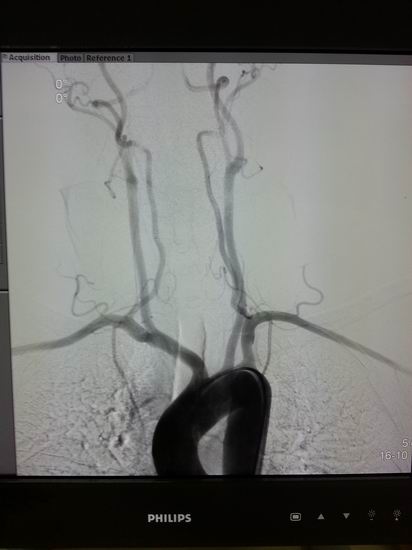

名称:高档数字减影、血管造影系统 Allura Xper FD20

主要功能:采用大平板科技,结合2K影像链,提供极佳图像细节解析能力,1250mA成像能力与“透心凉”高散热球管,“Refresh light”技术消除动态采集时的鬼影,图像质量更高。